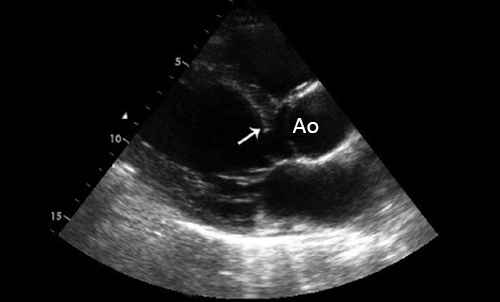

Эхокардиография при митральном стенозе

Причиной стеноза митрального клапана обычно является ревматизм. Редко стеноз МК может быть врожденным, связанным с дегенеративной кальцификацией, гиперэозипофилией, инфекционным эндокардитом, влиянием радиации и лекарственных препаратов. Типичные признаки ревматического стеноза МК можно обнаружить при ЭхоКГ в М- и В-режимах. Площадь отверстия МК измеряют планиметрически в парастернальной позиции по короткой оси. Трехмерная ЭхоКГ позволяет лучше определить площадь отверстия клапана у больных со стенозом МК или у перенесших комиссуротомию.

4. Эхокардиография (УЗИ-сердца) - является основным методом диагностики и оценки прогноза больных с аортальным стенозом. При этом возможна визуализация структур корня аорты и выносящего тракта левого желудочка, оценка подвижности створок и их состояния, определение локализации стеноза.